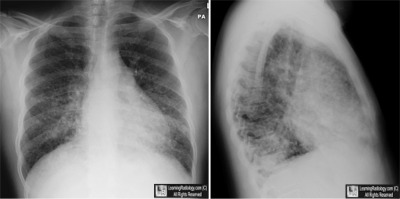

Frontal and Lateral Radiographs of the Chest

3. Pneumocystis Pneumonia

Pneumocystis Pneumonia

- Most common cause of interstitial pneumonia in immunocompromised patients

- Organism

- Protozoan / fungus Pneumocystis carinii (jiroveci)